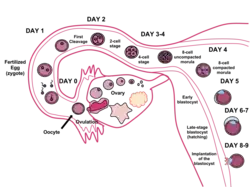

Внутриутробное развитие человека принято разделять на периоды. Развитие эмбриона от оплодотворения яйцеклетки до начала имплантации (первая неделя развития) характеризуют как преимплантационный период (см. Зачатие у человека), последующее развитие относят к постимплантационному периоду. В преимплантационный период эмбрион не прикреплён к стенке матки матери, в течение первых 4 дней эмбрион движется от места оплодотворения (ампулярная часть маточной трубы) по фаллопиевой трубе в сторону матки, на 5-6 день развития эмбрион находится в матке женщины подготавливая себя к имплантации (см. Zona pellucida). Также принято выделять эмбриональный (первые 8 недель от оплодотворения) и фетальный (от 9 недели до родов) периоды развития. В течение эмбрионального периода происходит пространственная организация первичных структур (морфогенез), начальная дифференцировка клеток и закладка систем органов (органогенез). В течение фетального периода происходит развитие органов в рамках сформированных систем, в значительной степени происходит увеличение размеров плода.

Эмбриональный период

Эмбриональный период длится от момента оплодотворения до конца 8 недели эмбрионального срока (10 неделя акушерского срока). В течение эмбрионального периода происходит эмбриогенез, в частности, такие процессы, как оплодотворение, дробление (образование многоклеточности), имплантация (внедрение в матку), гаструляция (образование зародышевых листков), гистогенез (формирование тканей), органогенез (формирование органов), плацентация и прочие процессы. В течение эмбрионального периода зародыш увеличивается в размере с 0,1 мм (оплодотворённая яйцеклетка) до 3 см (без учёта плодных оболочек). Изначально зародыш не напоминает младенца и лишь постепенно он приобретает черты и строение, сходные с младенцем. На последней неделе эмбрионального срока у эмбриона исчезают некоторые эмбриональные структуры (жаберные дуги и жаберные щели, хвост, уменьшается аллантоис).